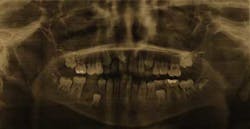

In June 2010, a healthy 9-year-old male presented to an oral and maxillofacial surgeon for evaluation of a lesion of right mandible No. 29 area. Panoramic radiograph Fig. 1revealed a mixed radiolucent radiopaque lesion in the area of missing tooth T and overlying the crown of developing tooth No. 29. Curettage of the area was performed and the tissue was placed in formalin and sent to the oral and maxillofacial pathology laboratory at The Mount Sinai Hospital in New York City.Fig. 1: Panoramic radiograph of a 9-year-old male reveals a mixed radiolucent — radiopaque lesion of the right mandible in the area of missing tooth T and overlying the crown of developing tooth No. 29.Fig. 2 demonstrates a fibrocollagneous cellular stroma containing scattered, small basophilic calcifications. A diagnosis of benign fibro-osseous lesion was made, and after radiographic correlation cemento-ossifying fibroma of bone was added to the final diagnosis.